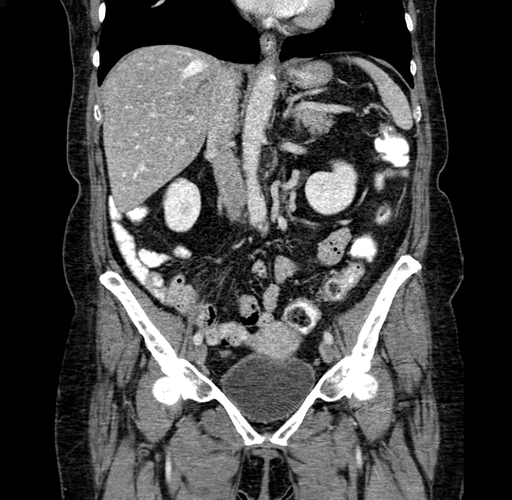

Axial Venous

Coronal Venous